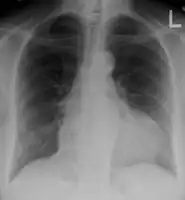

The diagnosis of tamponade can be confirmed with trans-thoracic echocardiography (TTE), which should show a large pericardial effusion and diastolic collapse of the right ventricle and right atrium. Chest X-ray usually shows an enlarged cardiac silhouette ("water bottle" appearance) and clear lungs. Pulmonary congestion is typically not seen because equalization of diastolic pressures constrains the pulmonary capillary wedge pressure to the intra-pericardial pressure (and all other diastolic pressures).

- Ultrasounds showing a pericardial effusion in someone with pericarditis

- A pericardial effusion as seen on CXR in someone with pericarditis